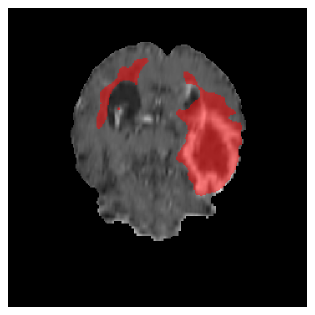

Figures 4 and 5 present the segmentation results for a patient from the BRATS dataset, visualized on a randomly selected slice. Figure 4 illustrates how tumor segmentation evolves over multiple episodes in S1 across different approaches including cumulative, naive, our approach, and the best buffer-free strategy (SI, =2). The cumulative approach, which trains on all encountered datasets together, maintains segmentation consistency across episodes but introduces significant amounts of false positives, particularly in the upper left area of the brain images. These misclassifications highlight its inability to generalize well across datasets despite access to all previous data. The naive approach, which learns sequentially without any continual learning strategy, suffers from severe catastrophic forgetting. While it initially segments well, performance deteriorates over episodes, leading to a near-complete loss of segmentation capability by the final episode. The SI (=2) approach, a regularization-based buffer-free CL strategy, performs reasonably well in early episodes but shows a significant performance decline over time. By the last episode, much of the tumor was no longer segmented, indicating difficulty in retaining prior knowledge. In contrast, our proposed approach initially produces more false positives but progressively refines its segmentation. By the final episode, it accurately retains the tumor region while minimizing misclassifications, demonstrating strong knowledge retention and adaptability across episodes. This suggests that our approach effectively mitigates catastrophic forgetting while maintaining segmentation performance over sequential learning.

Figure 5 illustrates the segmentation evolution for the same BRATS patient in S2 sequence. The key difference here is that the best buffer-free strategy is EWC (=1), and training on BRATS data starts from episode 2 instead of episode 1 as BRATS is encountered at episode 2 in S2. The cumulative approach retains segmentation across episodes but continues to generate false positives, which become even more pronounced in the final episode. The naive approach, lacking a CL mechanisms, completely overrides previous knowledge, leading to failed segmentation in later episodes. EWC (=1) approach initially maintains segmentation but experiences a sharp decline in episode 4, where it fails to segment the tumor. In the final episode, it undersegments the lesion, missing a significant portion of the tumor. In contrast, the proposed approach consistently preserves segmentation across episodes. While initially introducing false positives, it gradually refines predictions, retaining the tumor region while minimizing misclassifications. It maintains clear tumor delineation by the final episode, demonstrating effective knowledge retention and adaptability throughout training.